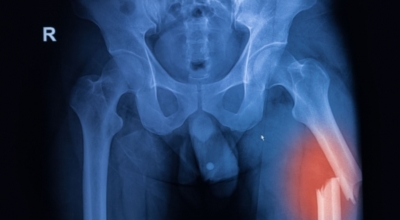

7. 콘드로이친 효능 - 골관절염

콘드로이친은 보통은 골관절염 증상 관리를 위한 치료제로 활용되고 있습니다. 미국에서 시행된 골관절염 환자 604명을 대상으로 한 연구에서 콘드로이틴의 골관절염 통증 관리의 효과를 관찰했는데 그 결과 콘드로이틴이 무릎 골관절염 통증이 있는 사람들의 약 10%가 통증완화와 개선효과를 체험했다고 합니다.

노화가 진행되는 중장년층에게서 콘드로이친 수치가 저하되는걸 볼 수 있습니다. 이는 곧 연골의 뼈와 뼈 사이 완충효과 또는 보호기능 약화로 이어지는데 이를 보충하면 관절염을 해결하는데 도움을 줘요. 그리고 콘드로이친은 관절세포를 재생시키는데 도움을 주고 외부 쇼크을 흡수, 고치는데에도 대단한 효과가 있습니다.